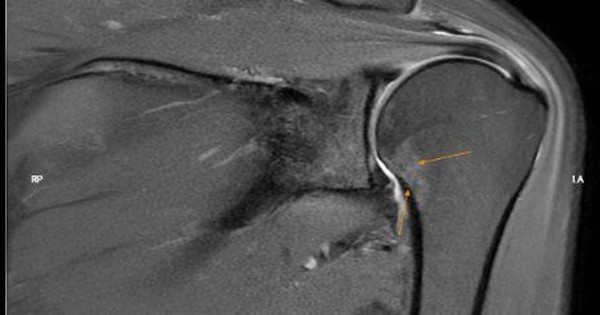

Hình ảnh phim chụp khớp vai trái bị đông cứng. (Ảnh bác sĩ cung cấp)

Kết quả chụp MRI khớp vai xác định tổn thương viêm, kèm theo hình ảnh của tổn thương khớp vai và xương cánh tay do thoái hóa. Kết quả chụp MRI cột sống cổ cho thấy tình trạng thoái hóa của đốt sống và đĩa đệm vùng cột sống cổ nhưng không gây chèn ép đám rối thần kinh cột sống cổ.